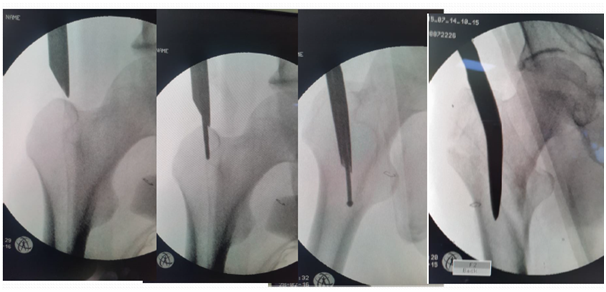

Entry point

1. Dead AP is 10 degree tilt of C arm.

2. Entry by guide wire and special sleeve with multiple options at the trochanteric tip (Figure 9).

Figure 9 Entry by guide wire and special sleeve with multiple options at the trochanteric tip.

For change of entry point

1. Use Special sleeve with multiple options (Figure 10).

2. Eccentric reaming by awl while keeping the first Guide wire is possible.

Figure 10 For change of entry point.